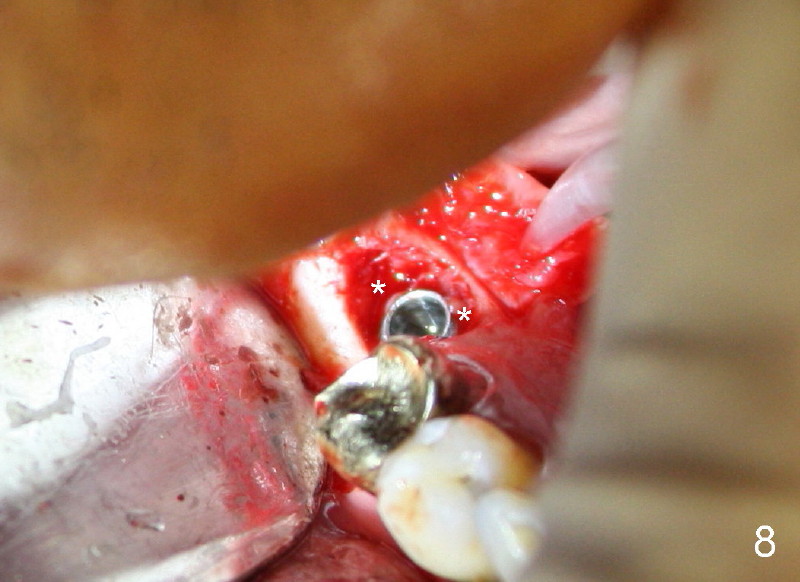

Unfortunately, there is bone resorption around the implant 3 months postop (Fig.6: >, as compared to Fig.4). Granulation tissue is present over the implant (Fig.7 *). The patient complains occasional pain and swelling after implant placement. Bone resorption is confirmed after removal of granulation tissue around the implant (Fig.8 *). After acid etch, Endogain (Fig.9 *, Straumann) is placed around the implant (P: healing plug). Flaps are approximated with 4-0 plain gut suture. Collagen membrane should have been used. Amoxicillin is prescribed, but the patient does not take it. It appears that bone graft to the sockets of #19 helps form an apparently continuous bone plate at the alveolar crest over the mesial (M in Fig.6') and distal (D) sockets, as compared to Fig.4'.